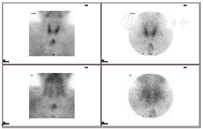

患者既往明确有2型糖尿病和高血压,入院后予皮下注射长效加餐时胰岛素降糖治疗,苯磺酸左旋氨氯地平和缬沙坦降压治疗。患者既往无慢性肾功能不全病史,本次入院初次发现慢性肾功能不全4期,既往无低钙抽搐病史,结合骨代谢指标提示患者高钙血症、高PTH,考虑诊断PHPT,但甲状旁腺超声未见明显异常,原发病灶尚不明确。考虑患者中度高钙血症,且临床症状明显,需给予降钙治疗,予生理盐水3 000 mL/d扩容、静推呋塞米(速尿)40 mg bid利尿和皮下注射鲑鱼降钙素100 IU tid促进尿钙排泄,降血钙治疗3天后血钙水平仍高,予单次静滴唑来膦酸4 mg治疗。胸部CT平扫提示前纵隔软组织影,予进一步完善18F-FDG全身代谢显像见前上纵隔软组织密度影,不伴明显代谢增高,良性病变可能性大,余处未见明显放射性异常浓聚区(图1)。结合胸部CT平扫和18F-FDG全身代谢显像结果,怀疑是否有胸腺瘤可能。因甲旁亢原发病灶仍不明确,需考虑是否有其他异位病灶。99mTc-MIBI双时相甲状旁腺显像示甲状腺下方、胸骨柄后方放射性异常浓聚灶,提示异位甲状旁腺伴功能亢进(图2)。行99mTc-MDP全身骨显像示左顶骨点状放射性摄取增高(图3)。因此,结合骨代谢指标及影像学表现,考虑诊断前上纵隔异位甲状旁腺腺瘤致PHPT。上腹部CT平扫:肝囊肿(12 mm×12 mm),胰腺未见明显异常,两侧肾上腺增生,右侧肾上腺髓样脂肪瘤可能(直径约15.5 mm),胆囊结石,左肾多发结石,右肾萎缩。胃泌素:59.89 pg/mL(25~100),血淀粉酶:81 U/L(28~100)。针对肾上腺相关内分泌激素检查:硫酸脱氢表雄酮、17-α羟孕酮、小剂量地塞米松抑制试验未见异常,立位肾素、血管紧张素、醛固酮指标正常,血儿茶酚胺水平正常。鞍区CT平扫见稍高密度影,但促肾上腺皮质激素及皮质醇节律、泌乳素、促性腺激素、胰岛素样生长因子1均正常,甲状腺超声提示甲状腺双侧叶结节TI-Rads 2类,甲状腺功能、甲状腺球蛋白、降钙素正常。降钙治疗6天后患者血钙水平降低至正常水平,考虑患者诊断为前上纵隔异位甲状旁腺腺瘤,定位明确且临床症状明显,手术切除异位腺瘤为最佳方案,患者出院后进一步于外院全麻下行胸腔镜纵隔内肿物切除术,纵隔内肿物:大小4.5 cm×3 cm×2 cm,病理诊断为:甲状旁腺腺瘤;免疫组化示:PTH(+),GATA(+),Rb(+),Bcl2(-),MDM2(+),CgA(+),Syn(-),CD56(-),Galectin3(-),CK(pan)(+),CK19(+),p63(-),CD34(血管+),Ki67(2%阳性)。术后第1天血钙为1.92 mmol/L,PTH为3.2 pmol/L。予10%葡萄糖酸钙20 mL/d静推,同时给予口服钙片和骨化三醇治疗,血钙逐渐恢复正常后出院。术后6个月后随访患者关节骨痛症状较前明显改善,肾功能较前明显好转,血尿酸425 μmol/L(143~420),血尿素6.7 mmol/L(2.5~6.4),血肌酐87 μmol/L(45~104),eGFR(CDK-EPI) 78 mL·min-1·(1.73 m2)-1(>90),血钙2.25 mmol/L,PTH为2.8 pmol/L,提示无甲状旁腺功能亢进复发。